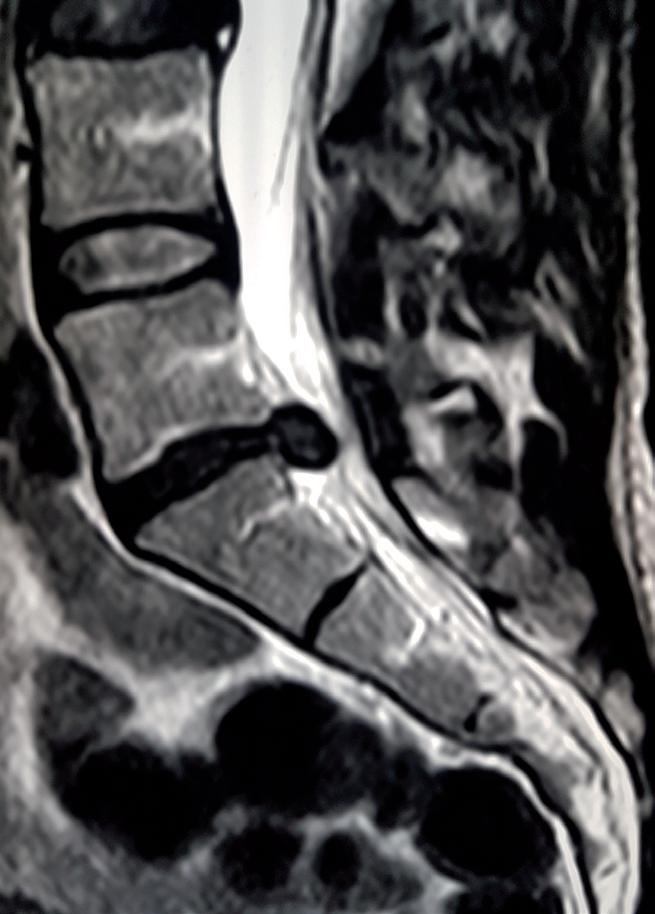

KURZ NOTIERT ... 66 IM INTERVIEW 68 Ladislav „Laci“ Legenstein WHO´S WHO 72 Boris Schwarz 3 FRAGEN – 3 ANTWORTEN 74 Timo Grober FIRMENPORTRAIT 76 Braun EDL PARTNERUNTERNEHMEN cook&more 80 epicto 82 HERZLICH WILLKOMMEN 84 KINDERSPORT 86 Kinder und Aufmerksamkeit LEISTUNGSSPORT & MEDIZIN 90 Sportmedizinische Untersuchung für die Leistungskinder und -jugendlichen der TARN